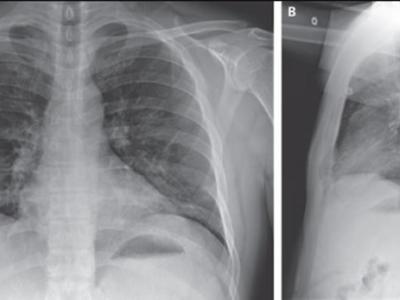

患者住院第6天的胸部X光(神秘的地球uux.cn报道)据ETtoday(詹雅婷、丁维瑀):各...